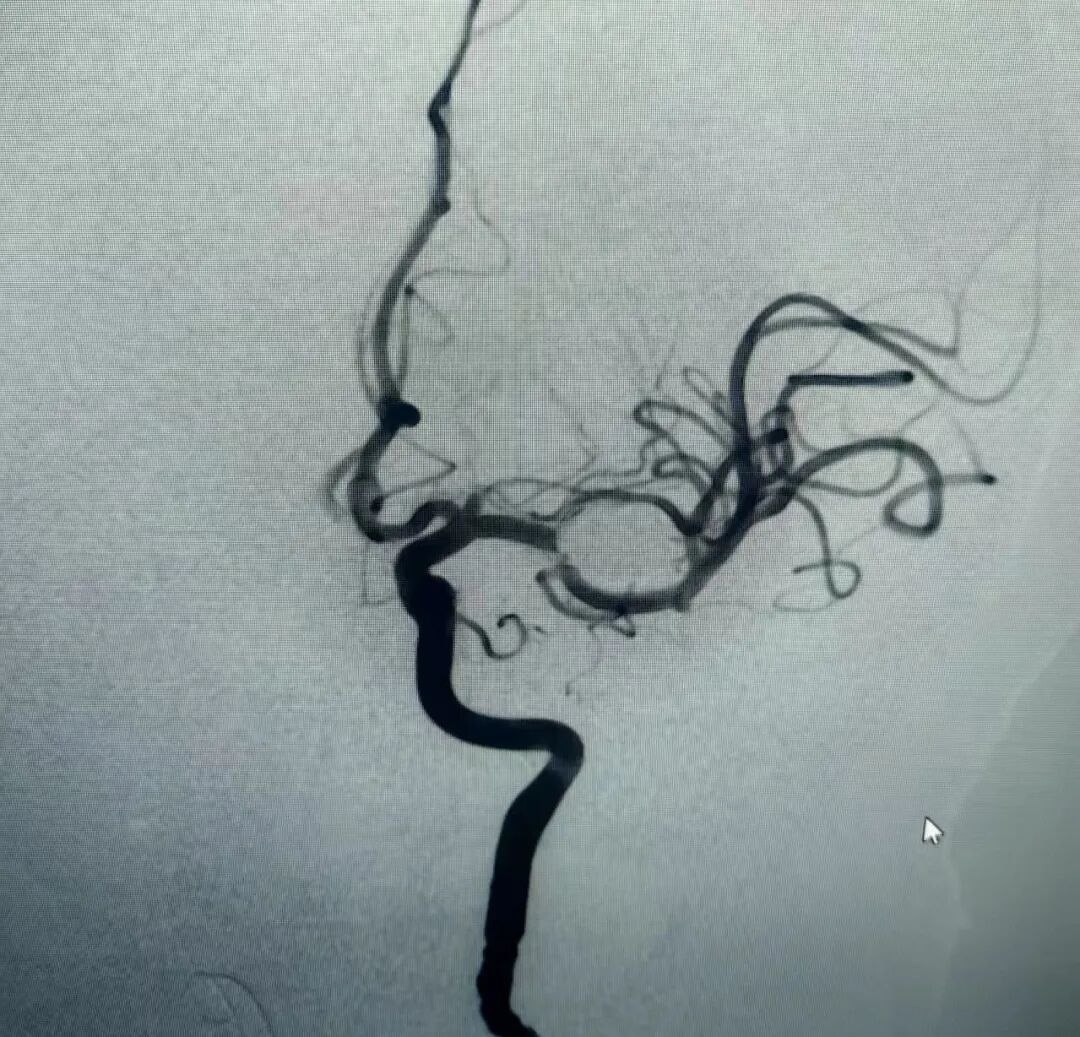

术前脑血管造影图

图片

手术当天,神经外科团队在麻醉科、介入室的密切配合下,通过股动脉穿刺,将微导管精准输送至动脉瘤腔,利用支架辅助技术固定弹簧圈,成功封闭瘤体,避免了开颅手术的巨大创伤。术后患者恢复良好,神经功能未受影响,现已康复出院。